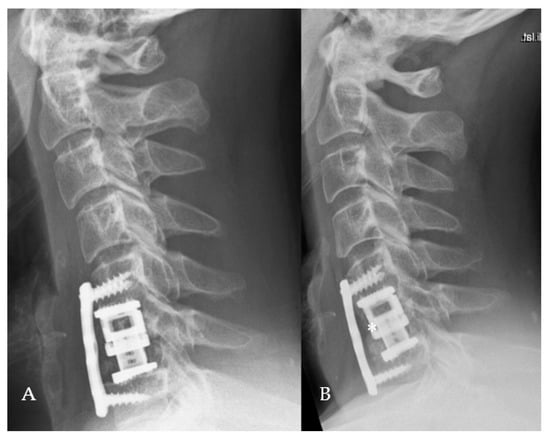

3.3. Complications